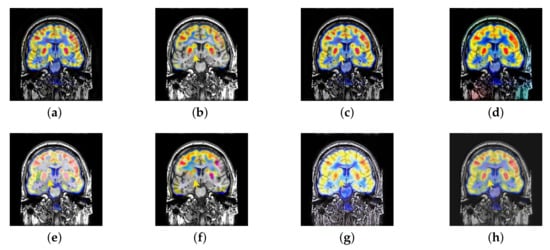

In this section, there are four image sets to fuse, each containing a MRI image and its corresponding CBF image in Figure 41. In Figure 42, Figure 43, Figure 44 and Figure 45, it can be seen that the structural information of fusion images obtained by our algorithm is complete. The color is not distorted, and the spectral features are natural. The fusion image based on DTCWT and NSCT algorithm have high color fidelity but less structural information. Other algorithms, such as IGM, LPSR, and FusionCNN, only focus on the structural information of the MRI image and ignore the color information of the fused image. Although the image structure information obtained by DDcGAN fusion algorithm is relatively complete, the edge of color information is not clear, which has a great influence on image contrast.

Figure 42.

Fused medical images obtained by different algorithms (Figure 41a,b): (a) DTCWT, (b) GFF, (c) NSCT, (d) LPSR, (e) IGM, (f) FusionCNN, (g) DDcGAN, and (h) FusionNet.

Figure 43.

Fused medical images obtained by different algorithms (Figure 41c,d): (a) DTCWT, (b) GFF, (c) NSCT, (d) LPSR, (e) IGM, (f) FusionCNN, (g) DDcGAN, and (h) FusionNet.

Figure 44.

Fused medical images obtained by different algorithms (Figure 41e,f): (a) DTCWT, (b) GFF, (c) NSCT, (d) LPSR, (e) IGM, (f) FusionCNN, (g) DDcGAN, and (h) FusionNet.

Figure 45.

Fused medical images obtained by different algorithms (Figure 41g,h): (a) DTCWT, (b) GFF, (c) NSCT, (d) LPSR, (e) IGM, (f) FusionCNN, (g) DDcGAN, and (h) FusionNet.